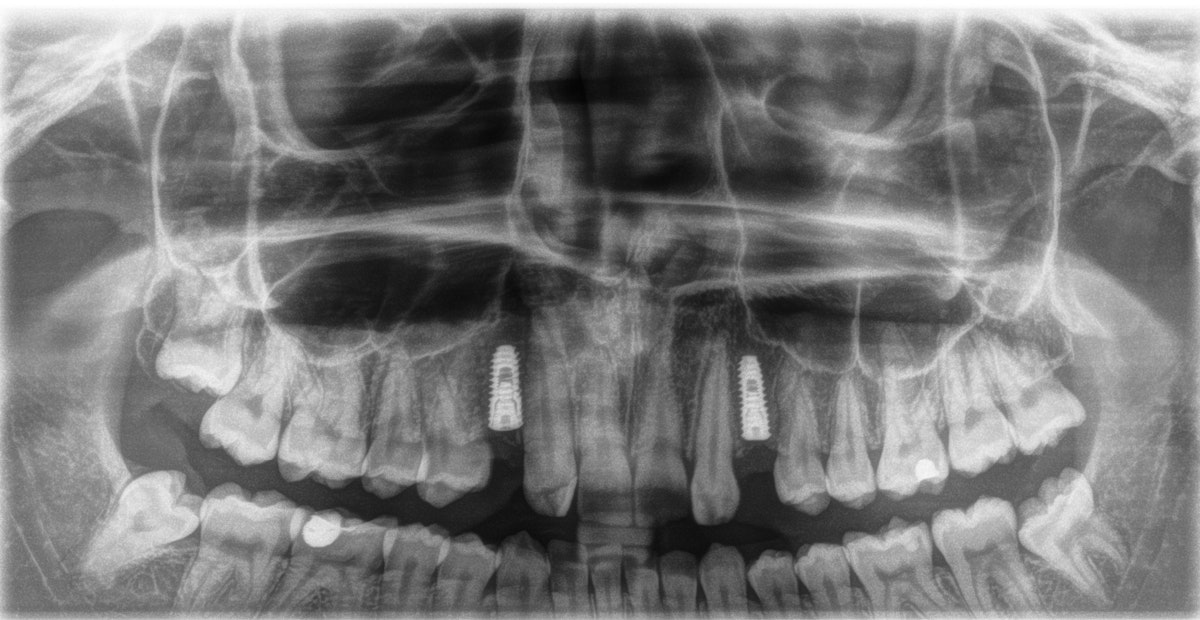

Radiologinen näkymä lopputilanteesta. Implanttikruunut paikoillaan.

Sama tilanne toiselta puolelta